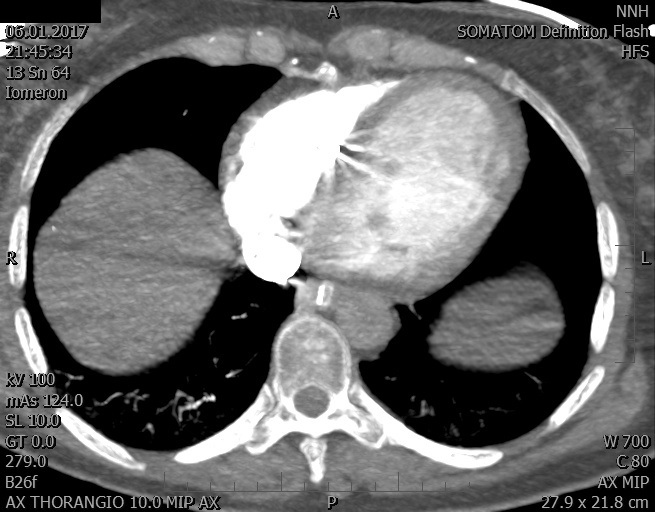

Video 1 - Akutní koronarografie prokázala normální nález na věnčitých tepnách s výjimkou suspekce na lehký spasmus na pravé koronární tepně.Echokardiograficky byla zjištěna těžká dysfunkce dilatované levé komory s nezvětšenou pravou komorou (video 2).

Video 2 - Echokardiograficky byla zjištěna těžká dysfunkce dilatační levé komory s nezvětšenou pravou komorou.Pro nejasnou příčinu zástavy jsme provedli i vyšetření výpočetní tomografií (CT), které vyloučilo plicní embolizaci (série 1 - soubory na konci článku). V den přijetí při přetrvávající oběhové nestabilitě byla nemocná opakovaně defibrilována pro fibrilaci komor se stabilizací rytmu po podání amiodaronu a mesocainu. Dle hemodynamických měření se jednalo o těžký kombinovaný šok. Vstupní laboratorní vyšetření bylo bez větších pozoruhodností. Posléze jsme doplnili anamnézu od příbuzných a zjistili, že pacientka užila do dvou hodin před srdeční zástavou první tabletu amoxicilinu na lehký respirační infekt. Při nevýtěžnosti vstupních vyšetření a nových anamnestických informacích jsme doplnili 14 hodin po kolapsu vyšetření koncentrace tryptázy v séru, která byla extrémně zvýšena (tabulka 2), což nás vedlo k podezření na anafylaxi.